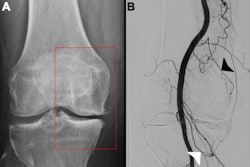

GAE and RFA are emerging minimally invasive procedures to treat the disease that may bridge the gap in treatment for patients who are refractory to medical management but are not yet eligible for or decline surgery, they added. Yet while the procedures both have promising supporting data, their wider adoption requires an understanding of their healthcare value relative to costs, the authors noted.